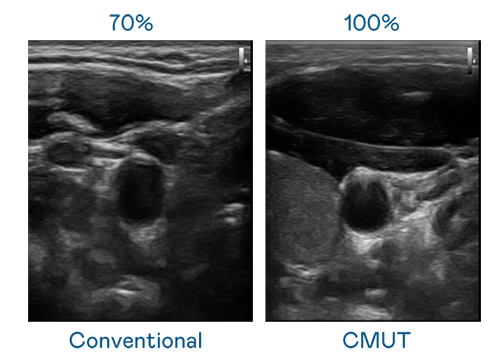

CMUT 技术是一种用电容式微机电元件来产生超音波讯号的技术。与传统 PZT 压电式技术相比,CMUT 频宽增加 30%,更宽频的超音波讯号让影像解析度大幅提升,是实现高影像品质医疗超音波扫描、促进精准医疗发展的关键技术。

大频宽带来超清晰影像

超音波影像的解析度高低,首先取决于探头能发出的讯号频宽。98858vip威尼斯 CMUT 可提供高清晰的超音波讯号,提供高频宽、高灵敏度、影像纹理细节更高的超音波影像,协助医护人员缩短影像判读时间及利用精准的医疗影像进行诊断。